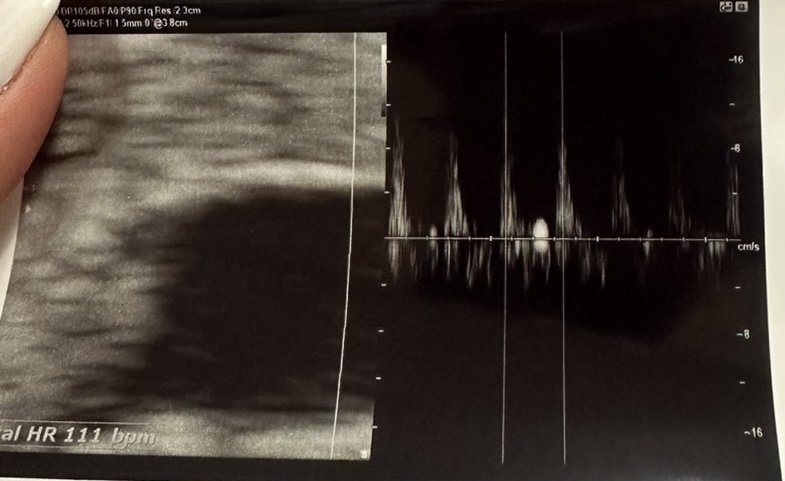

Здравейте,

Според вас големината на ембриона дали е добре за седмицата в която съм? Все си мисля че е много малко. Следващия ми преглед е на 14.04. Има много време и все го мисля. Макар доктора да каза Честито, чухме и пулс. За първи път ми е и е много дълго чакано,  затова малко се притеснявам. Благодаря!